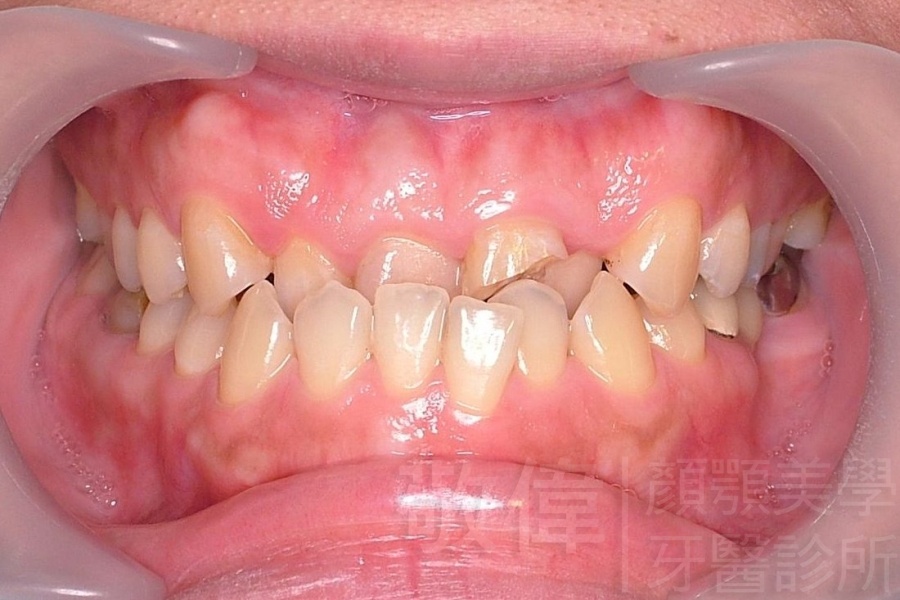

齒顏矯正/戽斗、亂牙、爛牙,變身 免植牙的健牙美女

<個案說明>

變臉矯正,原來戽斗妹跟大歪臉變成自信正妹

經由本院3D數影X光影像儀分析、與3D齒顎顏矯正技術,再配合口腔顎面正顎專科醫師施以正顎手術治療,雙方共同合作,使患者臉部外觀有很好的改善,大歪變小歪,產生了天南地北的大改變,她的人生也整個變得不一樣。

因為矯正與正顎手術的配合,使「戽斗妹」變成了「陽光正妹」,完全的改變了她的人生,在面對各種場合、與人交際都散發出自信微笑。所以,奉勸家長,如果小朋友有臉顎畸型的問題,應該考慮配合做這種簡單、安全、有效的正顎手術。